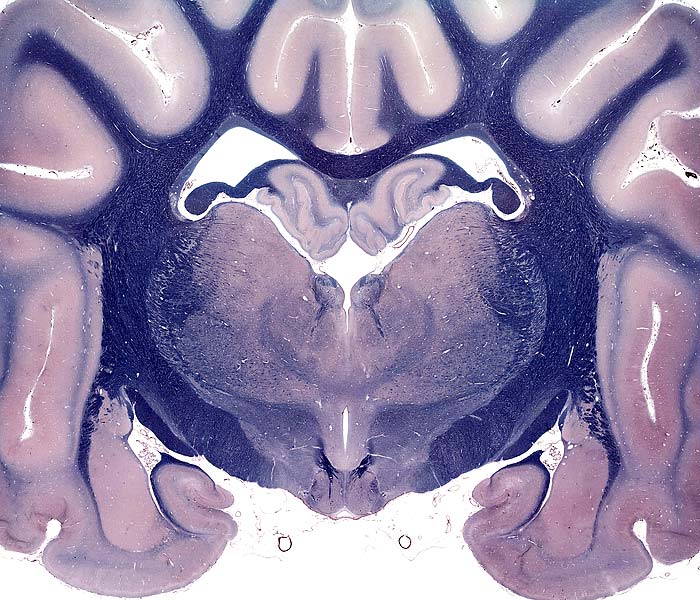

Transection: Mamillary Nucleus and Piriform Lobe

Telencephalon

Cerebral hemisphere

gray matter

cerebral cortex (neocortex)

cingulate gyrus

white matter

corpus callosum

internal capsule

ventricles

lateral ventricle

rhinencephalon

piriform lobe

amygdala (basal nucleus)

hippocampus

fornix

Diencephalon

thalamus

interthalamic adhesion

hypothalamus

mamillary body

habenular nuc.(epithalamus)

subthalamus

third ventricle

optic tract